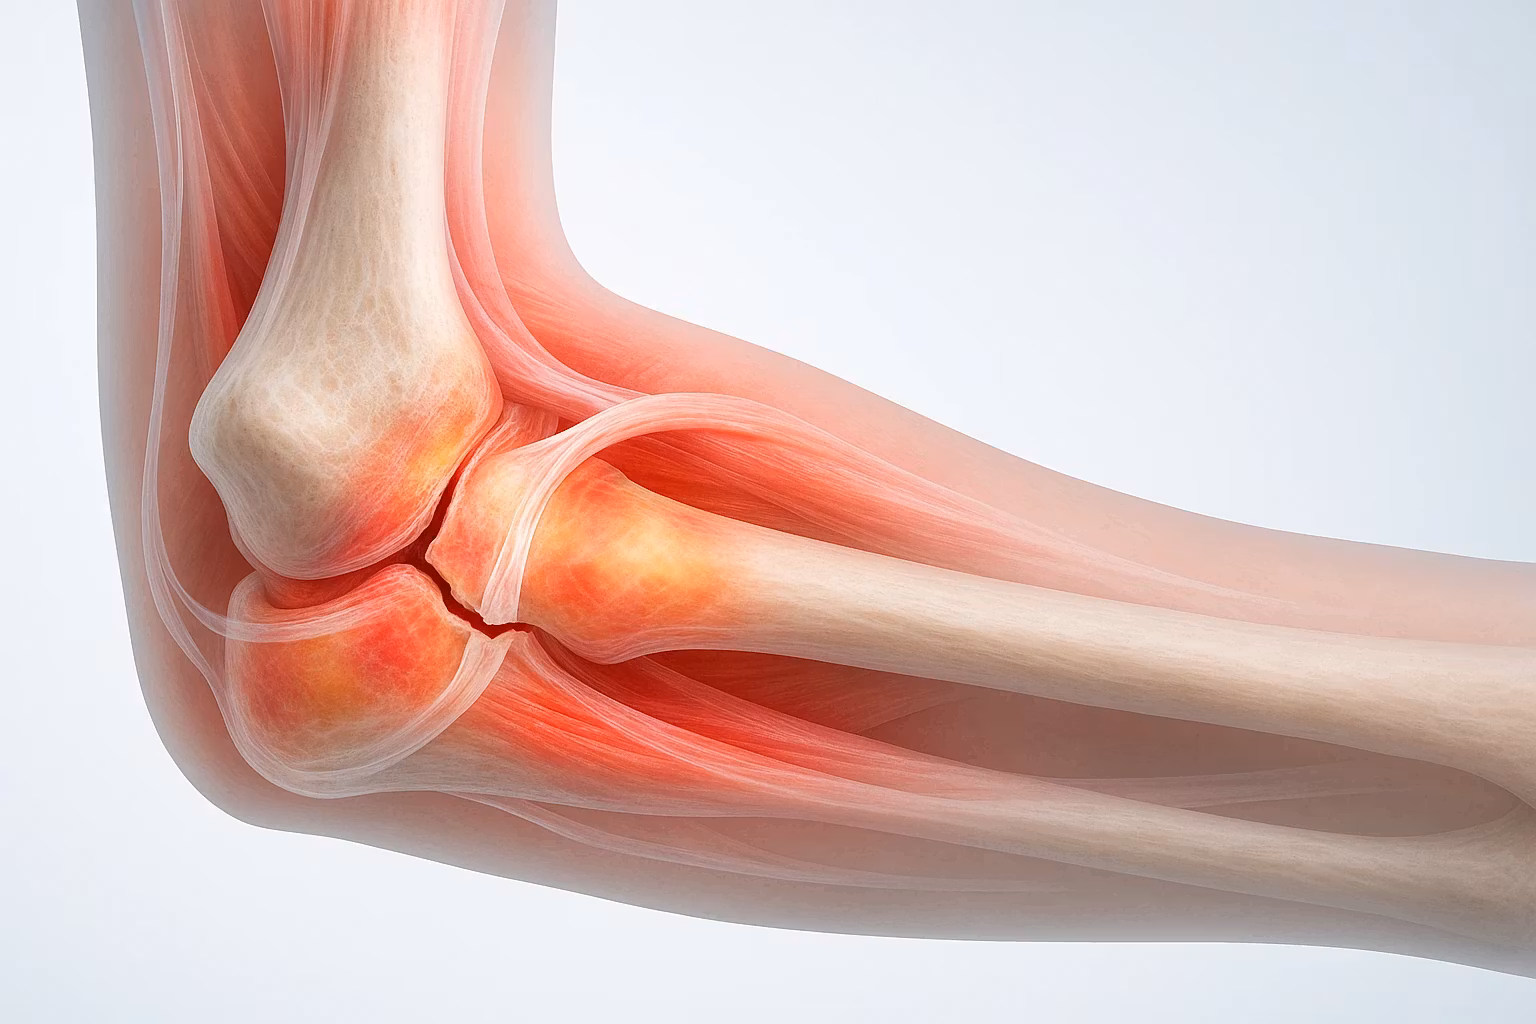

- درمان شکستگی ها و دررفتگی های اندام فوقانی و تحتانی

- آسیب های ورزشی از قبیل کشیدگی ها